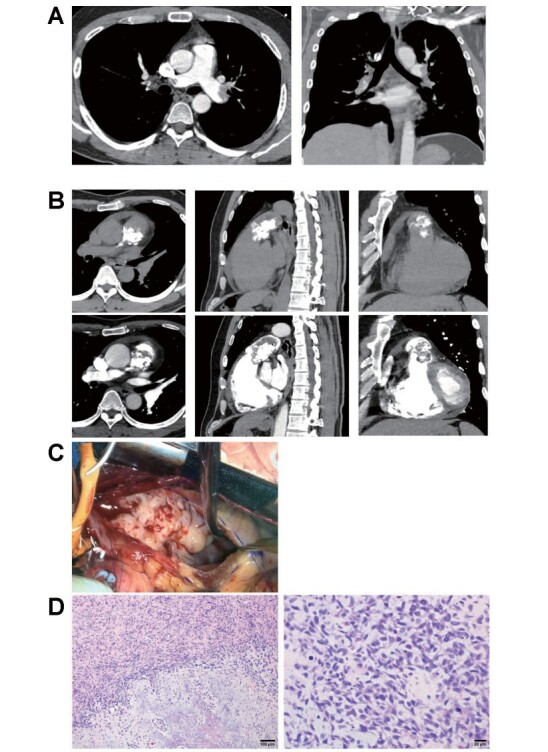

Acute Pulmonary Embolism: The Clinical Value of Early Follow-Up Computed Tomography Imaging in Thrombus Regression and Rare Differential Diagnoses of Pulmonary Intimal Sarcoma.